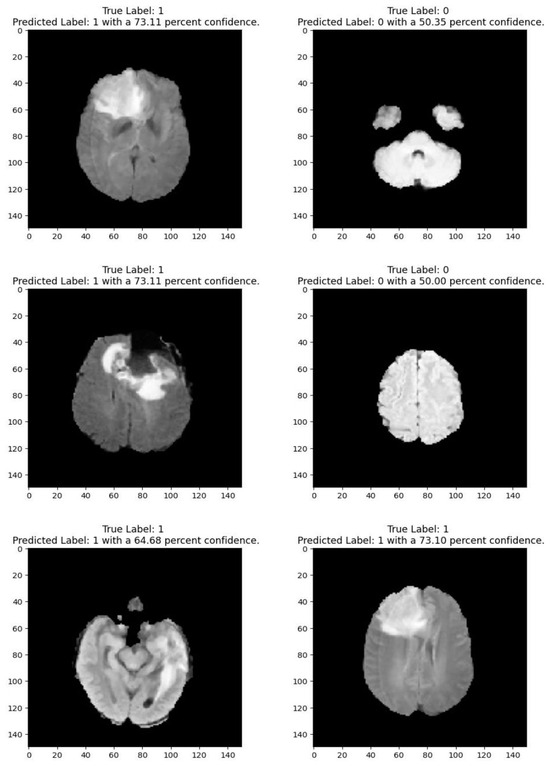

Medical imaging encompasses a diverse array of variations, underscoring the significance of image detection in their interpretation. Our focus was on utilizing MRI scans for the detection of brain tumors. MRI serves as a common modality for both detecting and categorizing brain tumors. In our study, we opted to employ fine-tuned transfer learning models to aid in the identification of brain tumors due to their ability to make precise predictions regarding tumor cells. Figure 9, Figure 10, Figure 11 and Figure 12 display graphical representations of the base model combined with transfer learning operations, and Table 4 presents the corresponding findings. Figure 13, Figure 14, Figure 15 and Figure 16 illustrate the epoch-by-epoch progress of the proposed model, with Table 5 summarizing the associated results. We present a comparison in Table 6 of this study, contrasting the existing research with our proposed approach. Figure 17, Figure 18, Figure 19 and Figure 20 represent the prediction of the model in terms of tumor or non-tumor. The model, named Fine-Tuned Transfer Learning Xception, achieved the highest accuracy of 0.9611, as indicated in the table.

Figure 2 shows that images depicting no tumor typically reveal a serene landscape of brain tissue, characterized by uniform intensity and well-defined anatomical structures. MRI images exhibiting tumors offer a stark contrast. Within these scans, areas of heightened intensity or irregular masses emerge, signaling the presence of pathological growths. These tumors may manifest as distinct lesions, irregular masses, or regions of increased signal intensity, disrupting the otherwise orderly landscape of brain tissue. Notably, the presence of tumors often induces observable changes in adjacent structures, which may appear compressed, displaced, or distorted. By discerning these visual cues, healthcare professionals can effectively differentiate between images with no tumor and those with tumors, facilitating accurate diagnosis and informed treatment decisions for patients

The comparative analysis of the brain tumor detection models highlights the varying performance of different architectures based on methodology and dataset. Traditional deep learning models such as a CNN (92.67% on BraTS 2018) and a DNN (93.10% on BraTS 2014) have shown strong results, while pre-trained architectures like VGG-19 (94.82% on CE-MRI) and Pre-trained CNN (94.58% on CE-MRI) have further improved accuracy by leveraging transfer learning. More advanced hybrid approaches, such as NS-CNN (95.62%) and XG-Ada-RF (95.90%), utilize ensemble techniques to enhance classification performance. The proposed fine-tuned transfer learning models demonstrate competitive and superior performances compared to prior studies. Among them, Xception achieves the highest accuracy of 96.11%, surpassing even ensemble-based techniques. This can be attributed to its depthwise separable convolutions, which optimize feature extraction while reducing computational complexity, making it highly effective for MRI-based classification. Additionally, MobileNetV2 (94.48%), VGG19 (92.46%), and InceptionResNetV2 (92.26%) further validate the effectiveness of fine-tuned transfer learning.